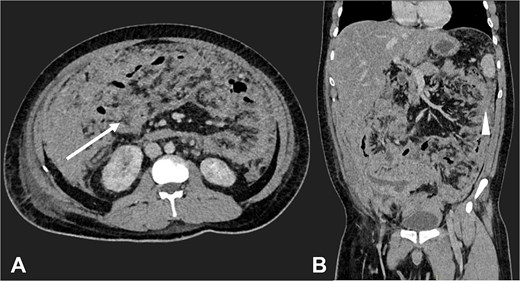

Postoperatively, suspected PTB was evaluated. Diagnostic tests, including sputum smear microscopy and GeneXpert MTB/RIF, peritoneal fluid culture and microscopy, and auramine-rhodamine stool staining, were negative. Thoracoabdominal CT (Figs 2 and 3) revealed generalized PC, plaque-like involvement at the hepatic flexure of the colon, and inflammatory lymph nodes. Histopathology provided the definitive diagnosis of NHL (Figs 4 and 5). Following an uneventful postoperative recovery, the patient was discharged after one week and referred to a tertiary care center, where chemotherapy was initiated, leading to significant improvement.

Contrast-enhanced CT in the venous phase: Axial view (A) and coronal reconstruction (B) demonstrated nodular thickening of the peritoneum with vascular enhancement, peritoneal implants measuring up to 6 mm (arrow), and plaque-like implants along the splenic margin (head arrow).